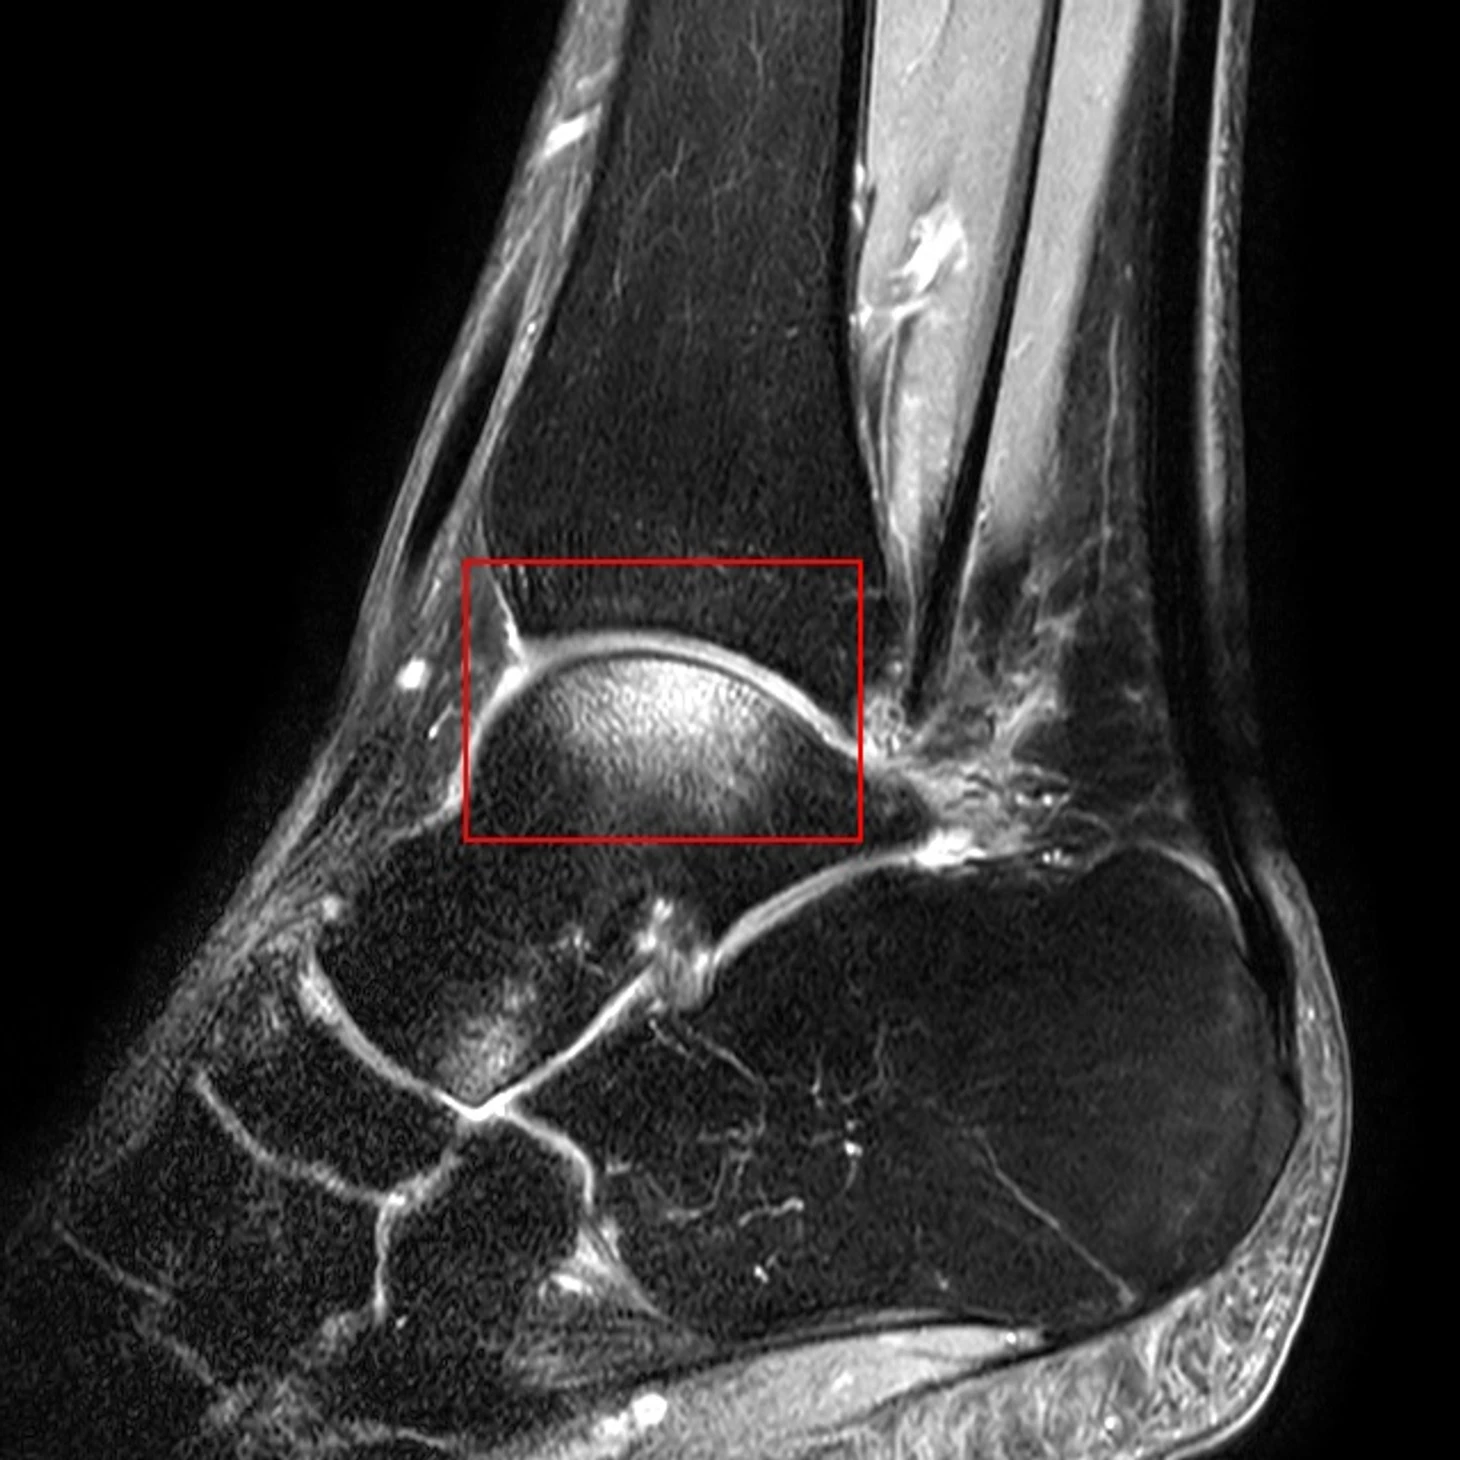

На МРТ в этом режиме жидкость и менее плотные ткани светлее, из-за чего хорошо видны связки и межкостные соединения, более темными будут кости и сухожилия. Красной рамкой выделено светлое пятно на таранной кости, одной из костей, образующих голеностопный сустав, это пятно и есть контузия.

Контузия в переводе с латыни буквально означает ушиб. Но когда речь идет о костной ткани, появляется ряд важных особенностей. Контузия кости – это отек ее внешнего слоя, надкостницы, в котором находятся нервы и сосуды, питающие кость. Из-за этого травма всегда крайне болезненна – крик Айртона, попавший в эфир, это подтвердит. Возникает этот отек либо при прямом ударе, либо опосредованно — при рывке мышц или связок в области мест их прикрепления к кости. Часто эти два фактора могут сочетаться вместе, поэтому руководитель пресс-службы »Спартака» Дмитрий Зеленов и сказал, что у Айртона контузия не только кости, но и окружающих тканей. Вот что могли увидеть врачи «Спартака» на МРТ.

Судя по механизму травмы Айртона, подозревали травму малоберцовой кости (это наружная лодыжка, «косточка», которая выпирает снаружи от голеностопного сустава); таранной кости, о которой говорилось выше, а также связок, прикрепляющихся в этих местах. В первую очередь это пяточно-малоберцовая и передняя таранно-малоберцовая. Еще в этой области проходит сухожилие длинной малоберцовой мышцы. Поэтому задача врачей не только снять отек, но и укрепить после этого пострадавший сустав, чтобы избежать его новых, но уже неконтактных травм. Для этого разрабатывается индивидуальный комплекс упражнений, которые постепенно усложняются и в конечном итоге подводят спортсмена к занятиям в общей группе. Вот один из примеров таких комплексов.